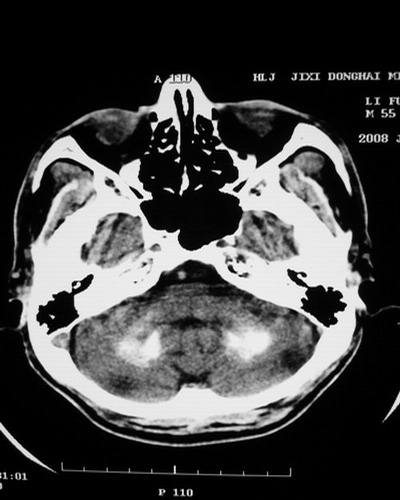

以下是引用随光逐影在2008-1-14 17:26:00的发言:[br]考虑为:甲状旁腺功能低下。需与fahr`s病相鉴别。建议:实验室检查。